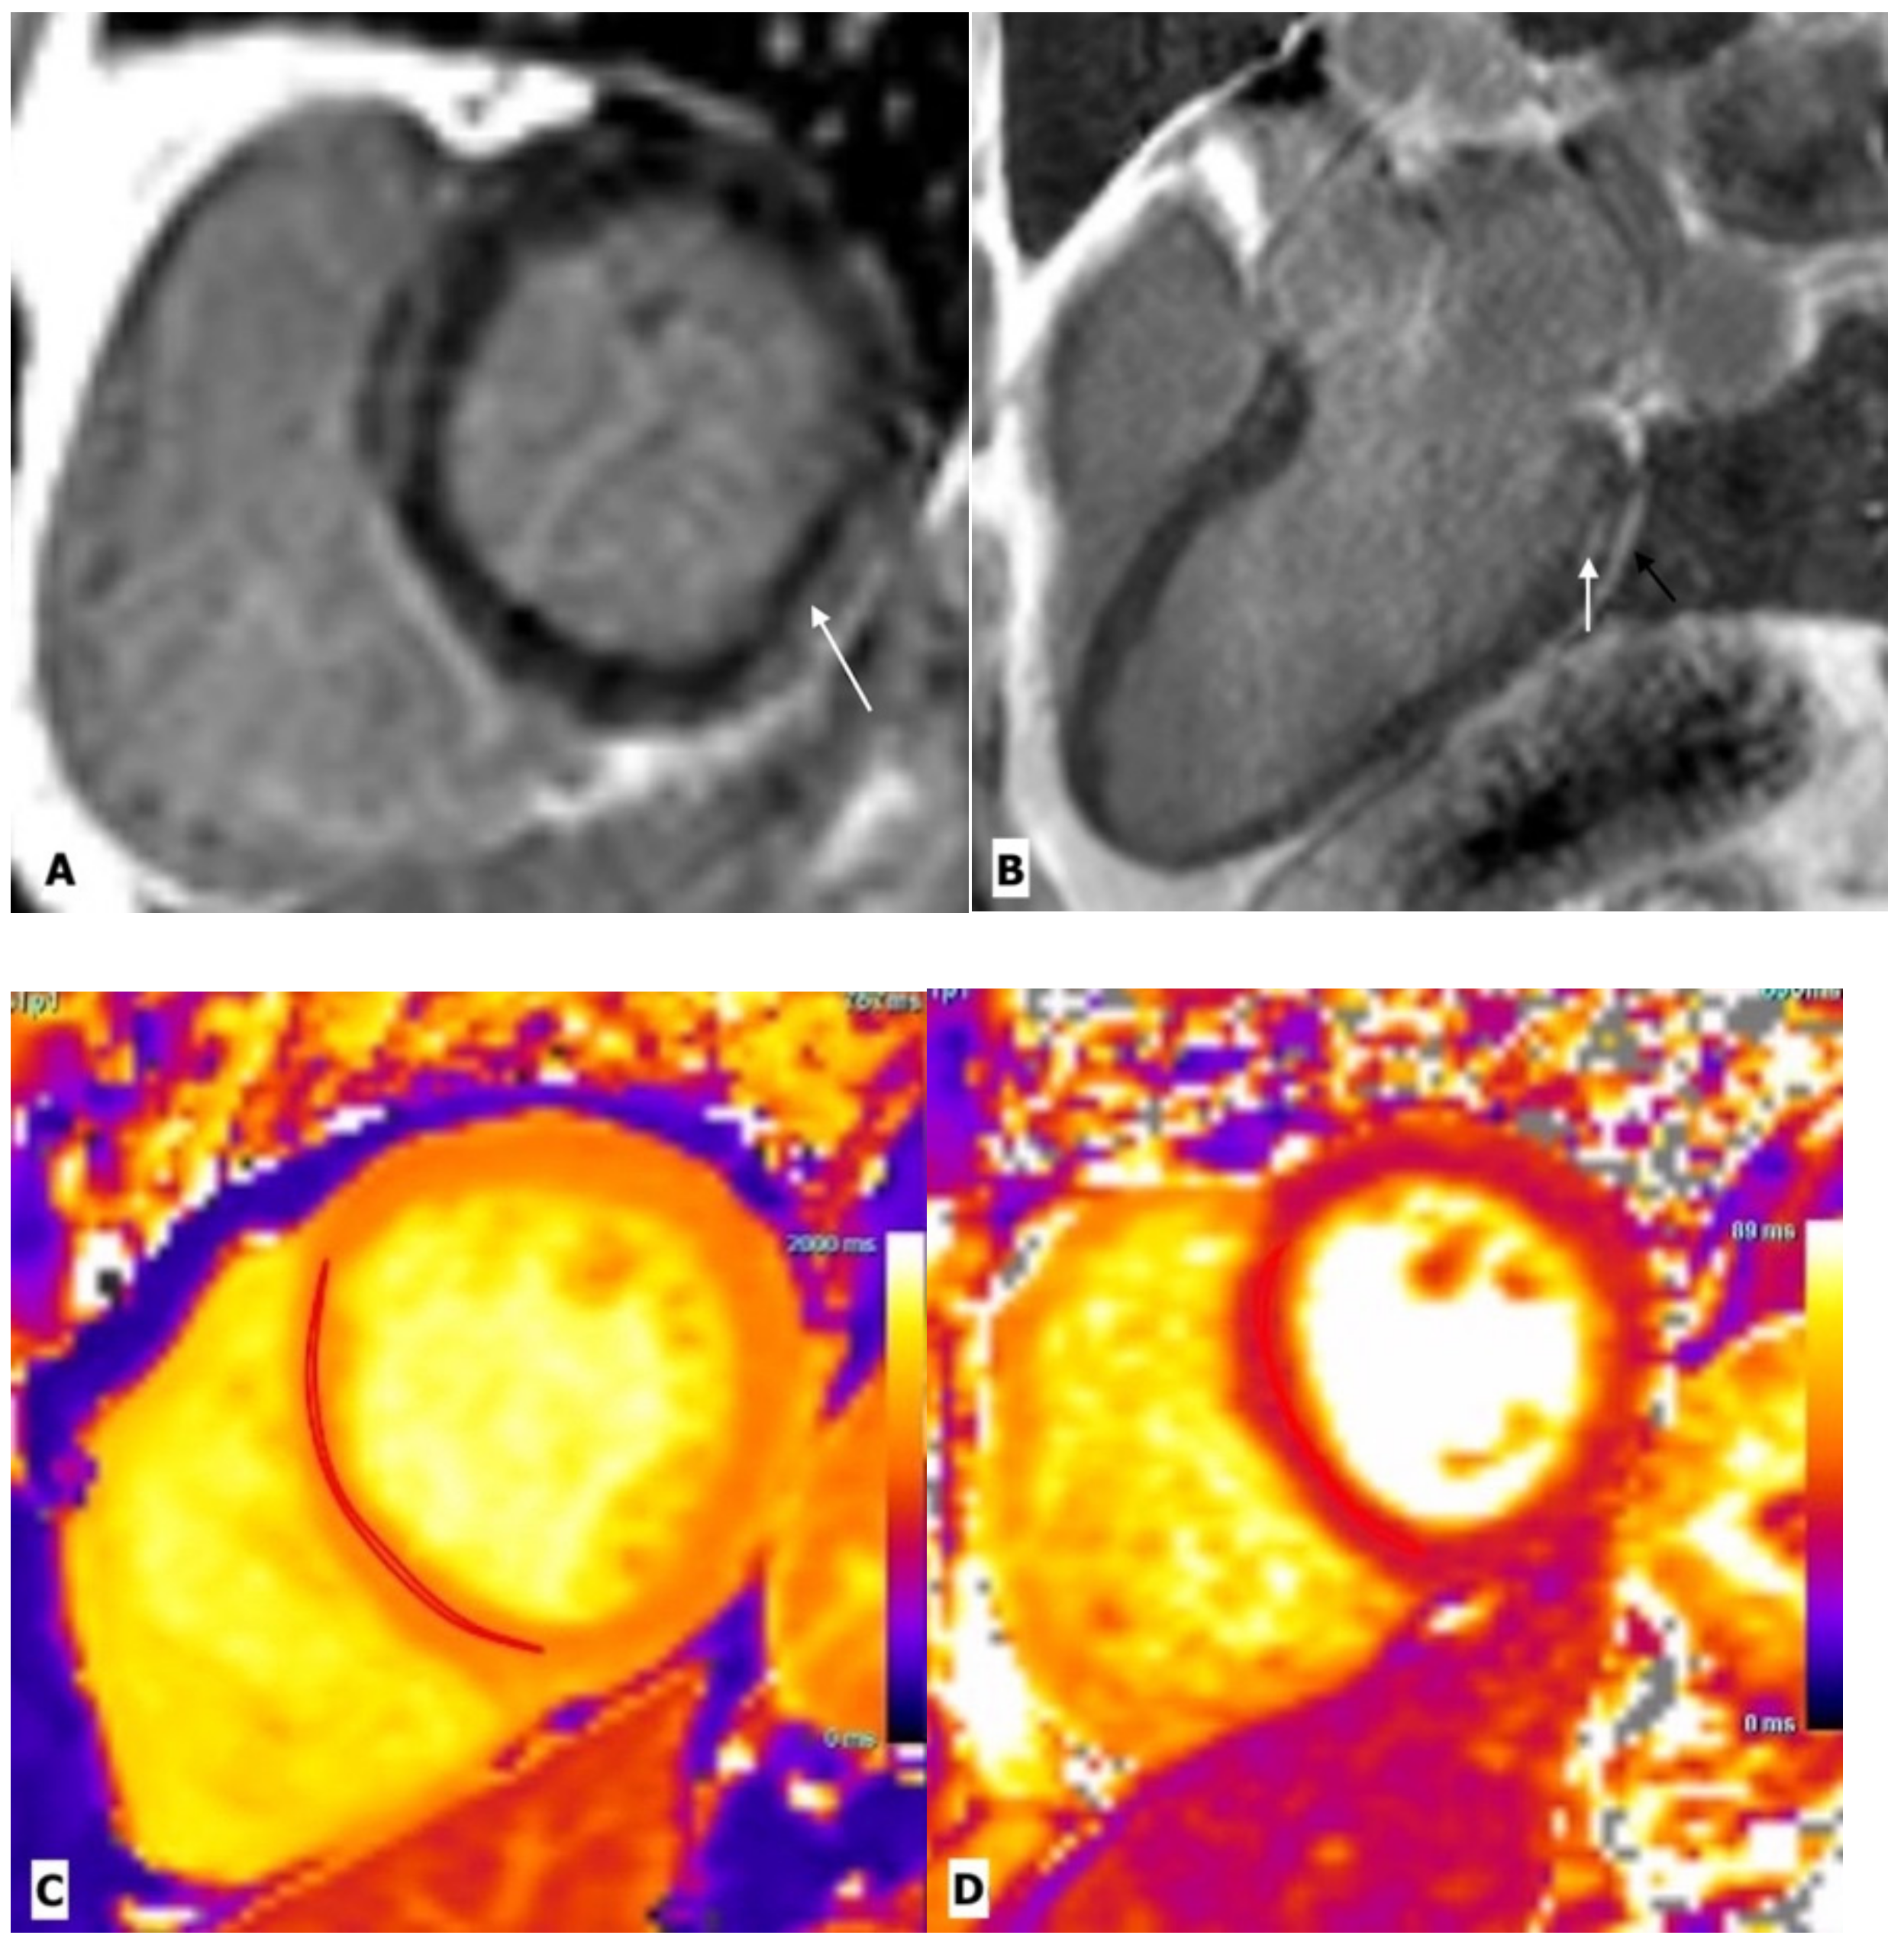

Figure 2.

Cardiac magnetic resonance imaging in a 43-year-old man with HIV-related perimyocarditis. (A) Mid-ventricular short-axis and (B) 3-chamber long-axis images showing linear mid-wall enhancement in the basal inferior and inferolateral lateral walls (white arrows). The overlying pericardium also shows mild thickening and enhancement. (C) T1 map and (D) T2 map at the mid-LV show a markedly elevated myocardial T1 time of 1214 ms (normal 1104 ms at 3.0 Tesla) and T2 time of 44 ms (normal 37.4 ms at 3.0 Tesla) consistent with diffuse myocardial fibrosis.